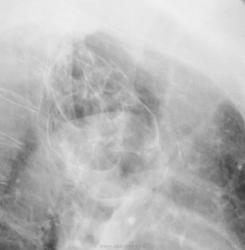

ХОБЛ+множественные кисты у бабушки.

Почему - не крупные бронхоэктазы?... ХОБЛ оспаривать, так понимаю, бесполезно))))

Большие они и круглые.

Жесть. Мыслей нет. По логике кисты. Но может и посттуберкульозные остатки. Может у автора КТ припрятано?)))

Почему кисты, а не буллы?

В буллах/бронхоэктазах есть менисковидные уровни жидкости - обострение. Картинки - красота, такое редко встречается.

По мягкотканным интересно, но я в этом не особо спец. Меня же заинтересовал 8 грудной позвонок (если я верно посчитал). Клиновидную деформацию со снижением высоты вижу. Была Шейермана-Мау? Или перелом в анамнезе? Или...?

Перелома в анамнезе не было.

А, какие данные за Шейермана?